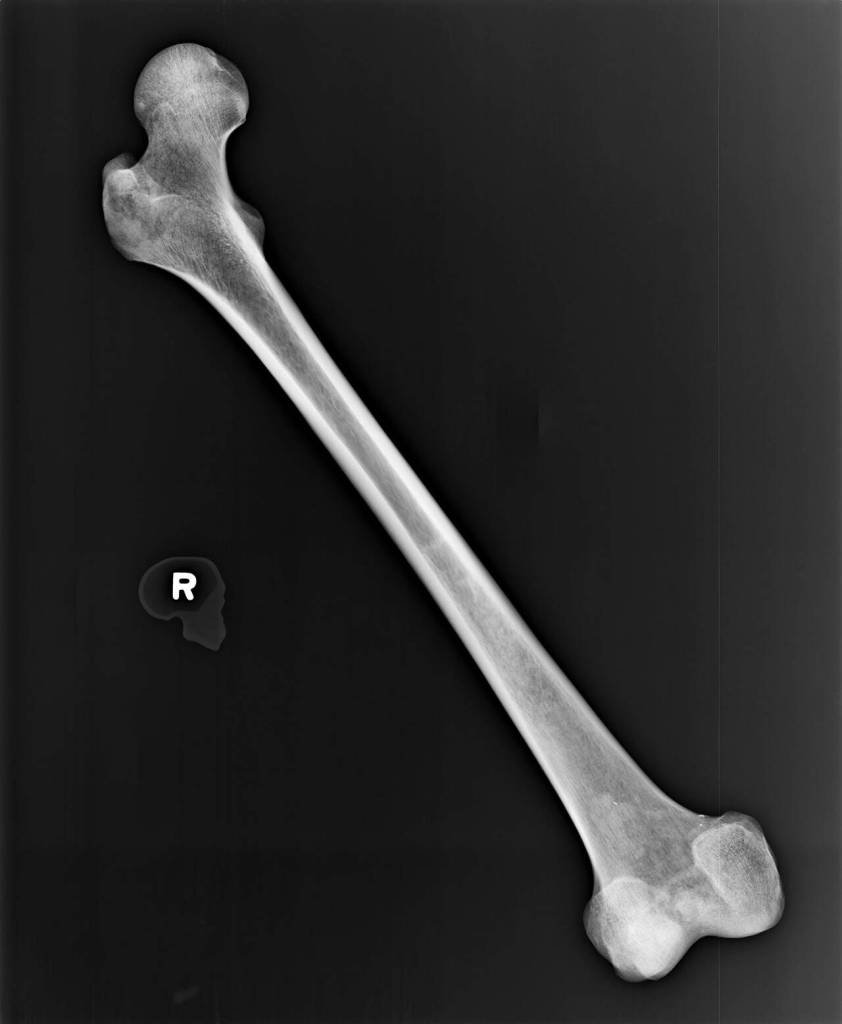

Dr. Kathy Taylor, a state forensic anthropologist, examined the exhumed bones, too. She estimated they belonged to a man with Caucasian ancestry, who stood from 5-foot-2 and and 5-foot-6. She guessed he could be anywhere from 27 to 61 years old. She saw no “perimortem trauma” — that is, trauma at or around the time of death — but she did note an unset left femur fracture that had healed awkwardly. It would’ve left him shuffling around in pain, likely for years, about 2 inches shorter on one side.

A section of the right femur was sent to the University of North Texas to extract DNA and upload it to the FBI’s database, CODIS. Those samples were obtained by March 2019. Death investigators ruled out many possible matches through DNA and dental records, but still they were without a name.